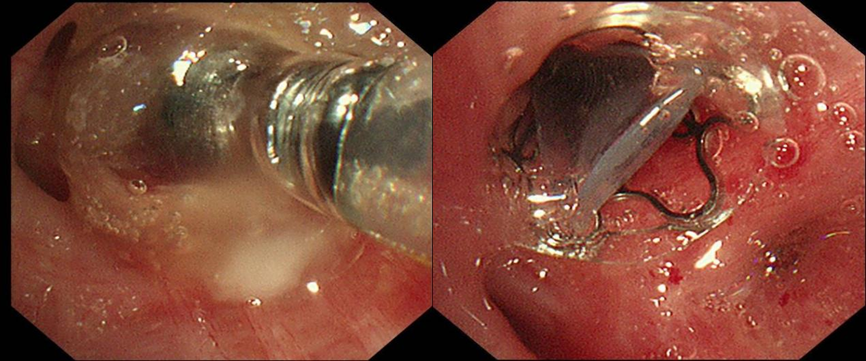

面对再次漏气,医疗团队果断进行再一次支气管镜介入。先置入可吸收明胶海绵,进行初步封堵,为后续操作创造更好条件。随后,精准释放EBV活瓣(EBV-TS-4.0),活瓣如同“智能阀门”,吸气时开放保证通气,呼气时关闭阻断气体漏入胸膜腔。术后膨肺并负压吸引,观察一分钟,引流瓶未见气泡溢出。三次支气管镜介入,阶梯式推进治疗,最终实现对支气管胸膜瘘的“精准打击”。

出院前复查气管镜于右上叶尖段见活瓣开口,局部予充分灌洗后未见气泡溢出,复查胸片提示右侧气胸较前明显吸收好转,困扰患者许久的胸腔闭式引流瓶终于得以拔除,王女士彻底告别了支气管胸膜瘘带来的阴霾。曾经,沉重的胸腔闭式引流瓶如影随形,严重限制了她的行动,如今,她终于能够轻松自在地行走。所使用的支气管内活瓣治疗也已纳入苏州医保,减轻了她的经济负担。出院之际,王女士难掩内心的感激流下了泪水,她紧紧握着蒋军红主任的手,言辞恳切地说到:“在患病的这段艰难日子里,是你们精湛的医术和无微不至的关怀,给了我重新生活的希望。每一次治疗,我都能感受到整个医疗团队的全力以赴。从病情诊断,到治疗方案的制定与实施,每一个环节都严谨细致,感谢蒋主任及各位医护人员。”